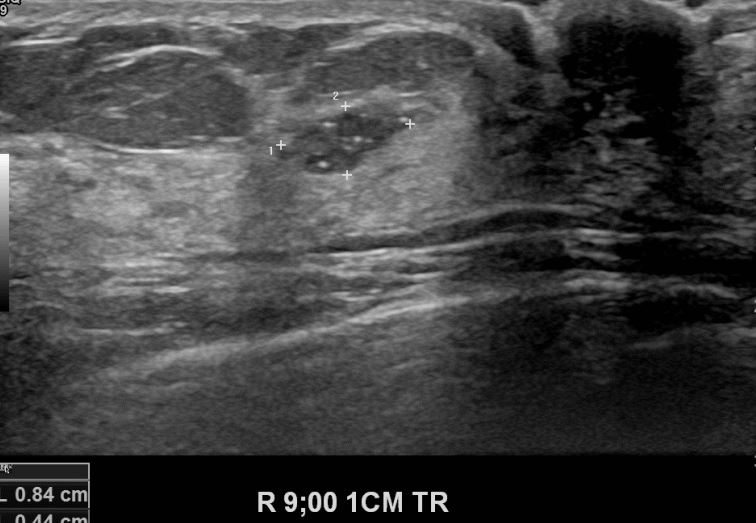

건강검진상 이상소견으로 내원하신 50대 여성분으로 초음파검사후 의심스러운혹

조직검사 시행후 유방암 진단되었읍니다